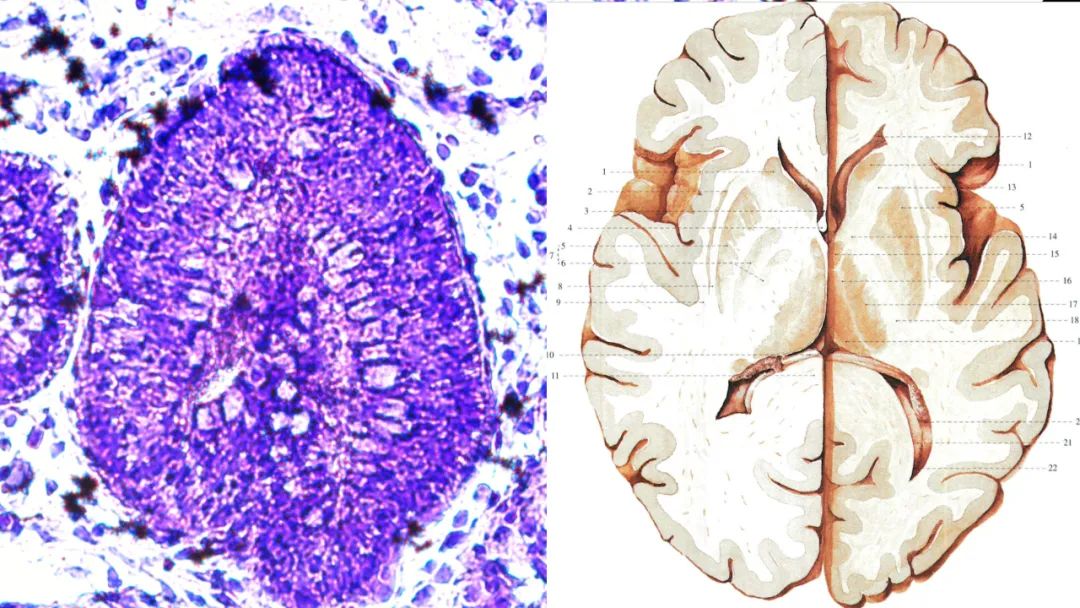

类器官领域,镁伽携手赛拉达生物,实现高通量标准化大规模类器官培养和测试。目前已成功培养出具有 2 波段跳动和显著腔室结构的心脏类器官、具有脑室和清晰神经结构的脑类器官等数十种具有极高价值的类器官模型。

类脑的形成